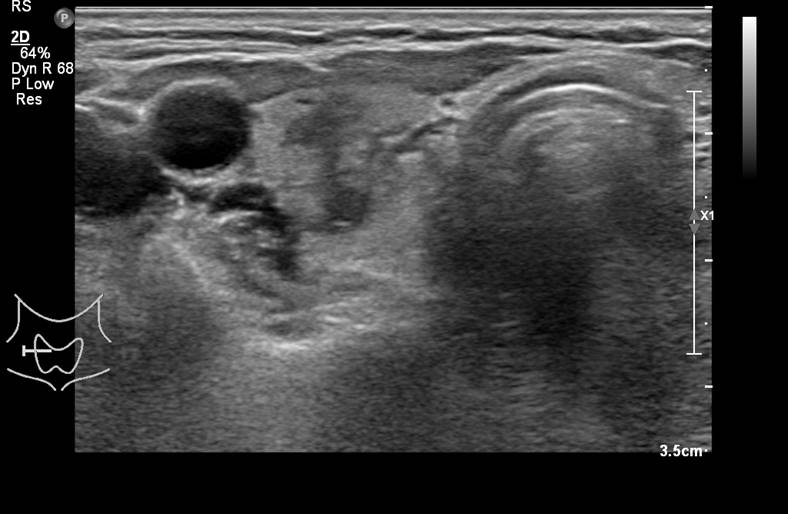

[360,] 64/F,Right anterior neck pain

다음 환자의 진단은?

Medullary thyroid carcinoma

Nodular hyperplasia

papillary thyroid carcinoma

follicular adenoma

Subacute thyroiditis